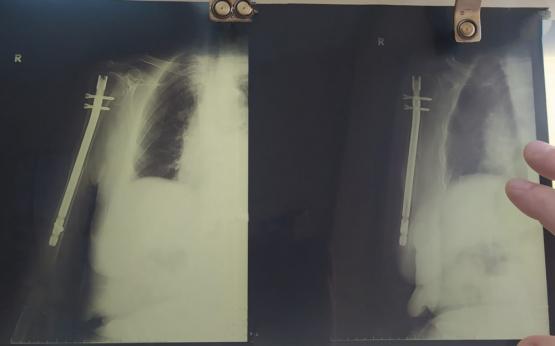

В  БСМП Ростове провели высокотехнологичную операцию 94-летней пациентке со сложным переломом плеча. Об этом сообщили в пресс-службе регионального министерства здравоохранения.

В начале лечения была применена региональная анестезия: у пациентки «отключили» только руку, на которой предстояло выполнить операцию. Сама она находилась в сознании. Затем была проведена операция по малоинвазивной технологии.

Это хирургический метод восстановления длинных трубчатых костей: через небольшие кожные разрезы в поврежденное место вводится специальный штифт, фиксирующий костные отломки. Зона перелома в процессе операции не открывается, что позволяет сохранить кровоснабжение и обеспечивает возможность быстрого сращивания перелома.

- Очень важно, что после проведения такой операции пациенту не требуется гипс и какие-либо сковывающие повязки. Что немаловажно для возрастных людей. Человек выписывается на пятый день после поступления. И далее наблюдается амбулаторно по месту жительства,  - рассказал врач травматолог-ортопед отделения травматологии № 1 ГБСМП Ростова-на-Дону Олег Литвиненко.

Сейчас 94-летняя женщина уже выписана из больницы. Врачи оценивают ее состояние  как удовлетворительное.